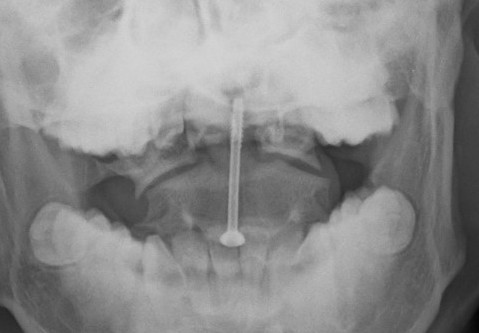

Odontoid screw

Ondontoid Screw Fixation

Advantages

Preserves C1/C2 cervical rotation compared to C1/2 fixation

Anterior Odontoid Screw Technique

AO Foundation Surgical Technique

Skull traction

Image intensifier

Smith-Robertson approach

Identify antero-inferior margin of C2

Results

- ondontoid screw fixation in 102 patients

- nonunion rate 4% in patients < 65 years

- nonunion rate 10% in patients > 65 years

- systematic review of odontoid screws

- 5% malposition

- 5% screw cut out

- 3% screw fracture rate

- nonunion 10%